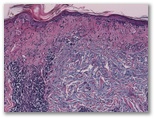

a) La dermatomiositis

b) el lupus eritematoso (dermatitis lupus)

c) Drogas - tipo de interfaz

d) El liquen plano, el tipo de parte atrófica

e) enfermedad de injerto contra huésped